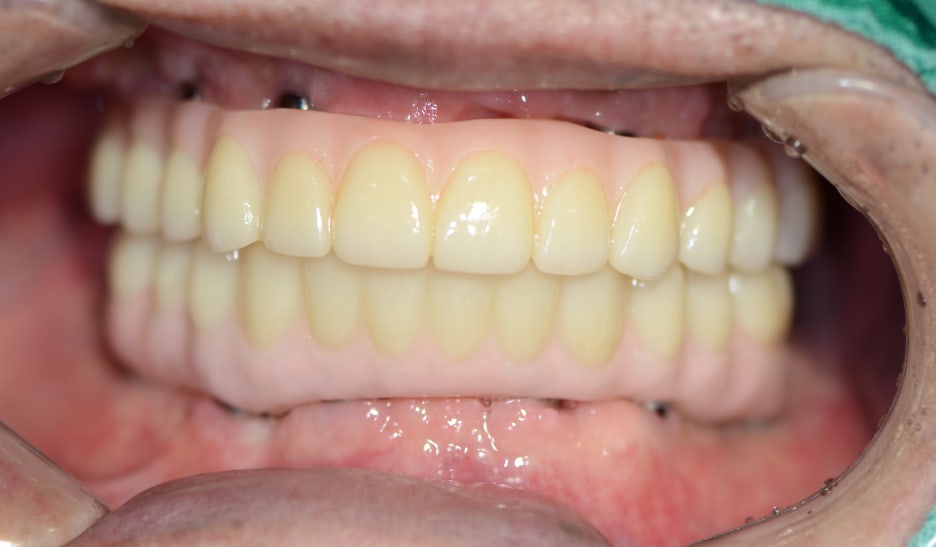

환자분께서는 뼈이식 없이

상악 6개, 하악 6개의

연제구임플란트를 식립하여 총 28개의

치아 기능을 회복하였고,

홀쭉하게 들어갔던 볼도

펴진 모습을 보실 수 있는데요.

진작 하실 걸 그랬다며 높은 만족감을 가지고 사용 중이세요.